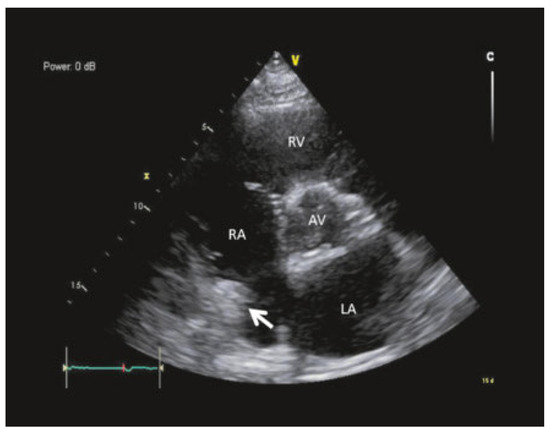

Atrial fibrillation is a cause of left atrial thrombus leading to cardioembolic stroke, which can be effectively prevented with oral anticoagulation. Right atrial appendage thrombus is a rare complication of atrial fibrillation that can also lead to cardioembolic pulmonary embolism. We present the case of a 71-year-old male with atrial fibrillation, thrombus in the right atrial appendage and pulmonary embolism. Full article

Show Figures

Figure 1